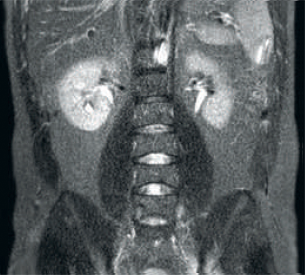

Resultado: resolución de imagen y SNR mejoradas

Resultado: imágenes ruidosas que usan parámetros de exploración idénticos

La tecnología de recepción de RF dStream digitaliza la señal del resonador magnético directamente en la bobina de radiofrecuencia, lo que resulta en un aumento de hasta un 40 % más de la SNR* en todo el volumen de la imagen.